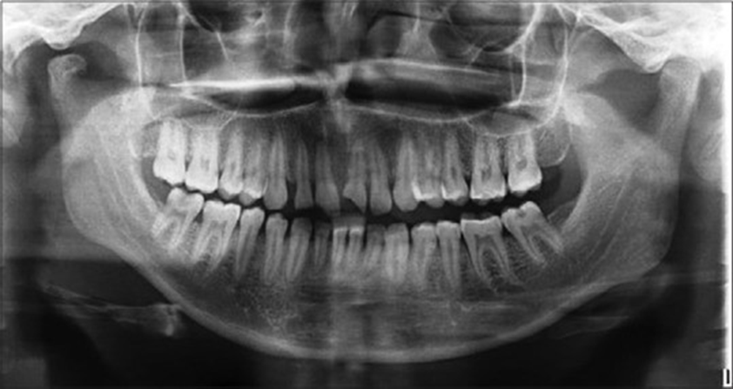

For all the patients who were considered for the said method, arch bar splinting of the maxilla and mandible and intermaxillary fixation was done with teeth in occlusion with the help of guiding elastics. Patients were systematically followed up at an interval of day 1, day 3, and weeks 1, 2, 4, and 6 postoperatively [Figures 2-7].

Figure 2: Preoperative orthopantomography